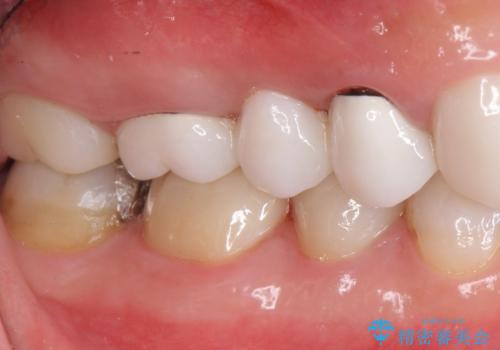

![[ 歯牙破折 ] 違和感のある大臼歯 ブリッジ治療の症例 治療前](https://seimitsushinbi.jp/wp/wp-content/uploads/2021/08/IMG_9577-500x350.jpg?v=1629711075)